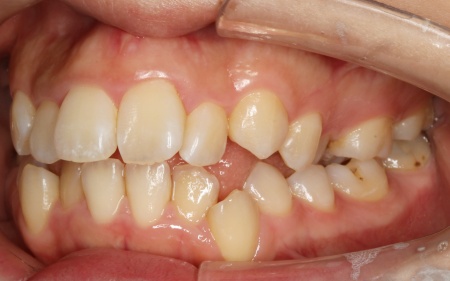

20代女性 ワイヤー矯正とマウスピース矯正を併用したハイブリッド矯正で歯並びを改善した症例

拝見したところ、上下の歯が正しく並ぶためのスペースが足りず、デコボコに生えていました。

とくに、犬歯が正しい歯並びから大きく飛び出した位置に生えており、いわゆる八重歯の状態です。

また、奥歯を噛み合わせた際に上下前歯が噛み合わず隙間ができる開咬(かいこう)も認められました。

矯正治療で歯を動かすスペースを確保するため、上左右奥歯2本(第2小臼歯)を抜く必要があることをお伝えしました。

また上下とも歯の移動量が多いため、ワイヤー矯正である程度移動を行ったのち、マウスピース矯正で仕上げを行う「ハイブリッド矯正」を提案しました。